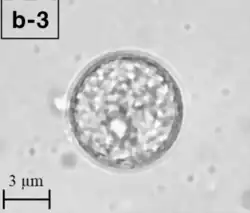

| Trophozoite (active) form of Balamuthia mandrillaris | |

B. mandrillaris is a free-living, heterotrophic amoeba, consisting of a standard complement of organelles surrounded by a three-layered cell wall (thought to be made of cellulose or a similar polysaccharide[8]), and with an abnormally large cell nucleus. On average, a Balamuthia trophozoite is about 30 to 120 μm in diameter. The cysts fall around this range, as well.[9]

Balamuthia's lifecycle, like the Acanthamoeba, consists of a cystic stage and a non-flagellated trophozoite stage, both of which are infectious, and both of which can be identified in the brain tissue on microscopic examination of brain biopsies performed on infected individuals. The trophozoite is pleomorphic and uninucleated, but binucleated forms are occasionally seen. Cysts are also uninucleated, possessing three walls: an outer thin irregular ectocyst, an inner thick endocyst, and a middle amorphous fibrillar mesocyst.[10]

Biopsies of skin lesions, sinuses, lungs, and the brain can detect of B. mandrillaris infection. The amoeba cannot be cultured on an agar plate coated with E. coli because, unlike Naegleria or Acanthamoeba, Balamuthia mandrillaris does not feed on bacteria. Instead, Balamuthia must be cultured on primate hepatocytes or human brain microvascular endothelial cells.[15] Formalin-fixed paraffinized biopsy specimens may indicate Balamuthia trophozoites in the perivascular space. The cysts can be visualized by calcofluor white, which binds to polysaccharides on the cyst wall. Trophozoites appear circular during infection.[14]